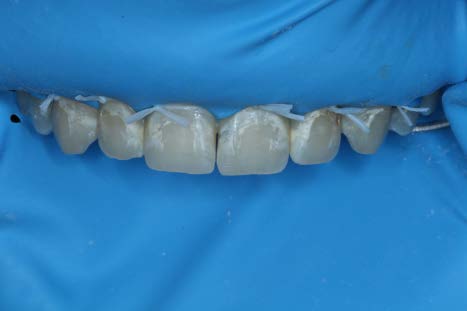

After allowing the Icon Dry to sit for 30 seconds and thoroughly drying the teeth, the resin Icon Infiltrant was applied for 3 minutes. The overhead light was removed and the resin was refreshed every minute. The excess resin was then blown away with an air-water tip and the teeth were flossed. Each tooth was then light cured for 40 seconds. A second round of infiltration was then applied, cured and a scaler was used to remove excess resin.

The patient and his mother were very pleased with the esthetic outcome. The patient had planned to return for a composite restoration for the cavitation on #10.

Interestingly, the cavitation on #10 felt hard to the touch with the tip and the explorer and relatively even with surrounding tooth structure.

We decided to monitor the lesion without surgical intervention at this time.